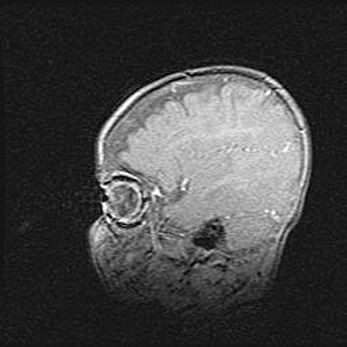

Сообщающаяся гидроцефалия. Кистозная энцефаломаляция головного мозга.

Возраст: 3 месяца 4 дня

Вес: 3100 г

Пол: женский

Окружность головы: 34 см

Срок гестации: 31 неделя

Кистозная энцефаломаляция головного мозга - одна из форм поражения головного мозга в детском возрасте. Характеризуется возникновением множественных и распространённых кист в коре, белом веществе и подкорковых образованиях головного мозга у плодов, новорождённых и детей раннего возраста. Развитие кистозной энцефаломаляции связано с внутриутробной асфиксией и гипотонией, родовой травмой, тромбозом синусов, пороками развития сосудов, инфекциями, сепсисом и другими причинами. Наиболее значимые инфекционные агенты: вирусы простого герпеса, цитомегалии, краснухи, токсоплазмы, энтеробактерии, золотистый стафилококк и другие.